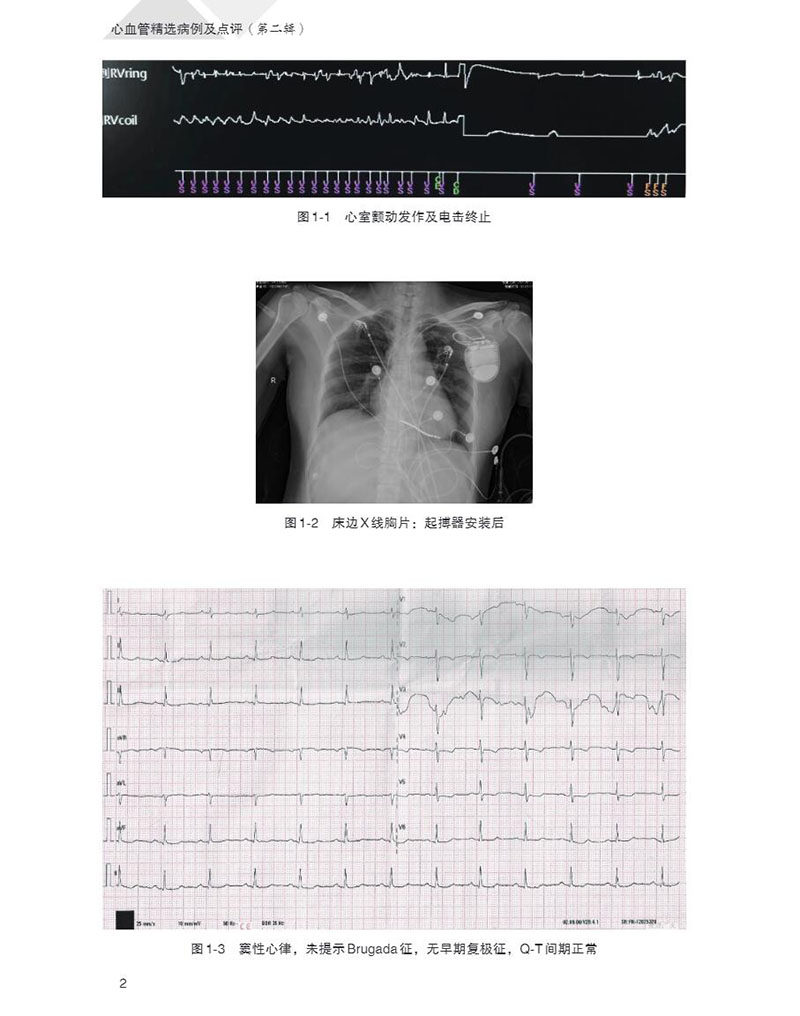

入院后:体温 36.3℃,脉搏 77次 /分,呼吸 16次 /分,血压 107/65mmHg,神志清楚,一般情况好。心脏及全身检查无异常体征发现。经起搏器远程监测证实此次晕厥为一次室颤发作,经电击使心律转复(图 1-1)。床旁胸片提示起搏器植入术后,心、肺正常(图 1-2)、心电正常(图 1-3)、动态血压正常,动态心电全程为窦性心律,偶发室性期前收缩和偶发室性心动过速(图 1-4)。超声心动图提示房室腔大小正常,二尖瓣和三尖瓣轻度关闭不全,左心功能正常。

图1-1 心室颤动发作及电击终止

图1-2 床边 X线胸片:起搏器安装后

图1-3 窦性心律,未提示 Brugada征,无早期复极征,Q -T间期正常